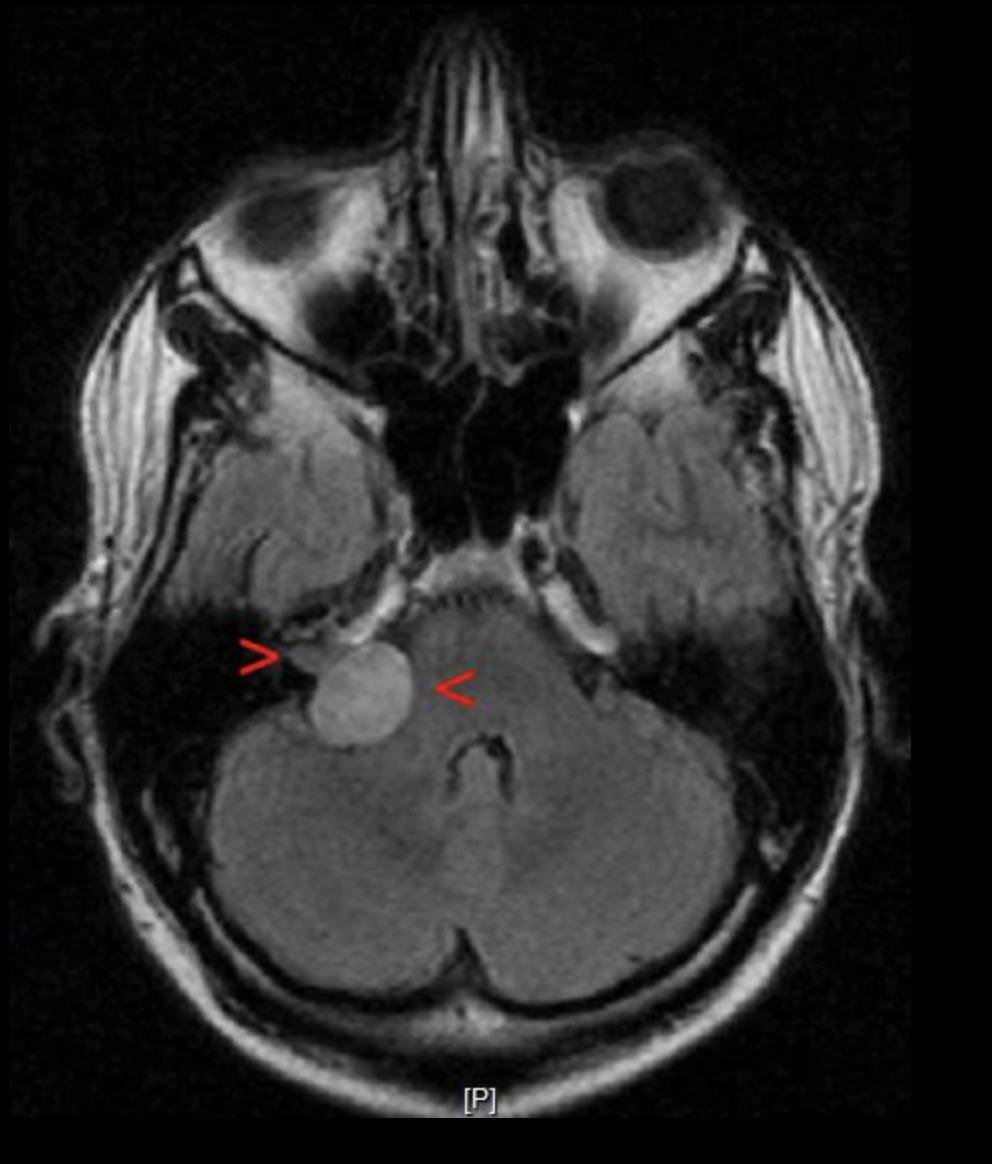

Не могу сказать, что это меня сильно волновало, потому что истинную причину этой проблемы я обнаружил случайно, по дороге к метро, переставляя наушник из одного уха в другое. Вскоре я побывал у трех разных ЛОРов и несколько раз прошел проверку слуха, которая подтвердила очевидное: слух на левое ухо снизился на 70%. После безуспешного поиска причины последний ЛОР направил меня к неврологу, а тот — на МРТ. И уже на снимках все стало ясно: вестибулярная шваннома, она же невринома слухового нерва.

Моя опухоль была 27 мм в диаметре, чего было достаточно, чтобы ее классифицировали как Koos IV, последнюю стадию по классификации Koos. В этом случае единственным вариантом является хирургическое лечение. Самым частым побочным эффектом операции считается парез лицевого нерва.